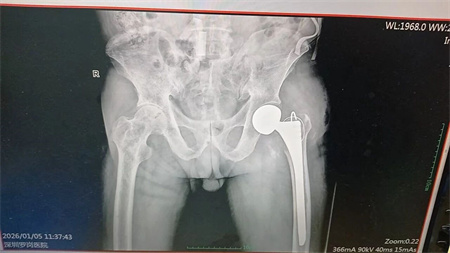

▲术前拍片